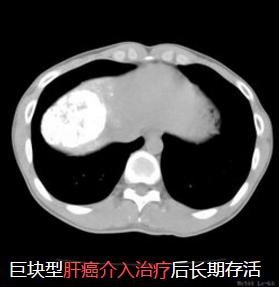

2、肿瘤性疾病方面:包括肿瘤的供血动脉栓塞与药物灌注、术前栓塞肿瘤血管、肿瘤经皮穿刺活检、射频消融、冷冻消融(氩氦刀)、放射性粒子植入等。